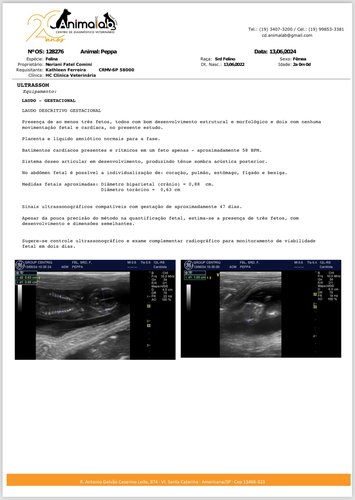

Ela foi encontrada no acesso a uma pista em Nova Odessa-SP (maio de 2024). Em consulta veterinária, testou positivo para a FeLV (Leucemia Viral Felina). O que eu jamais imaginava é que ela também estava prenha de 6 bebês em óbito, cada um num tempo gestacional diferente. Até que eu descobrisse a gravidez, se passaram 3 semanas após um primeiro ultrassom que não identificou nenhuma alteração nesse sentido. Por estar muito conectada com ela, comecei a ficar angustiada e procurei um segundo US: bingo! Corremos para fazer uma cirurgia/cesária de emergência. Salvei ela pela segunda vez!🥹

Laudo gestacional + cirurgia (cesária/castração):

No laudo foram visualizados 3, mas eram 6 fetos, todos já sem vida. Ela ter resistido super bem já é um milagre! Vitória na guerra, queridos.